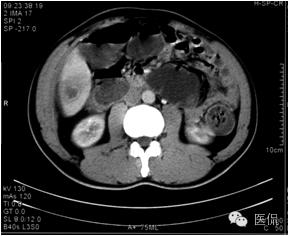

延迟期密度略有降落,但仍有强化,形态不规则。

手术病理诊断:

肝炎性假瘤,侵及周围结肠和腹壁,浸润组织有水肿,粘连。